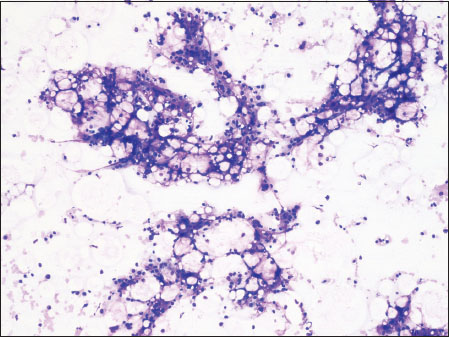

Bone marrow aspiration was done. The smears were paucicellular with adipocyte fragments and scant hematopoietic elements. There were no features of dyspoiesis in any lineage [Figure 2].

| Figure.2Bone marrow aspirate showing hypocellular marrow particles (×10)

In addition, the patient had pancytopenia which suggested the possibility of an infiltrative disorder of bone marrow. Bone marrow metastasis of malignant melanoma presenting as pancytopenia has already been reported in cases with XP.[10] In our patient, bone marrow aspirate and trephine were consistent with aplastic anemia.